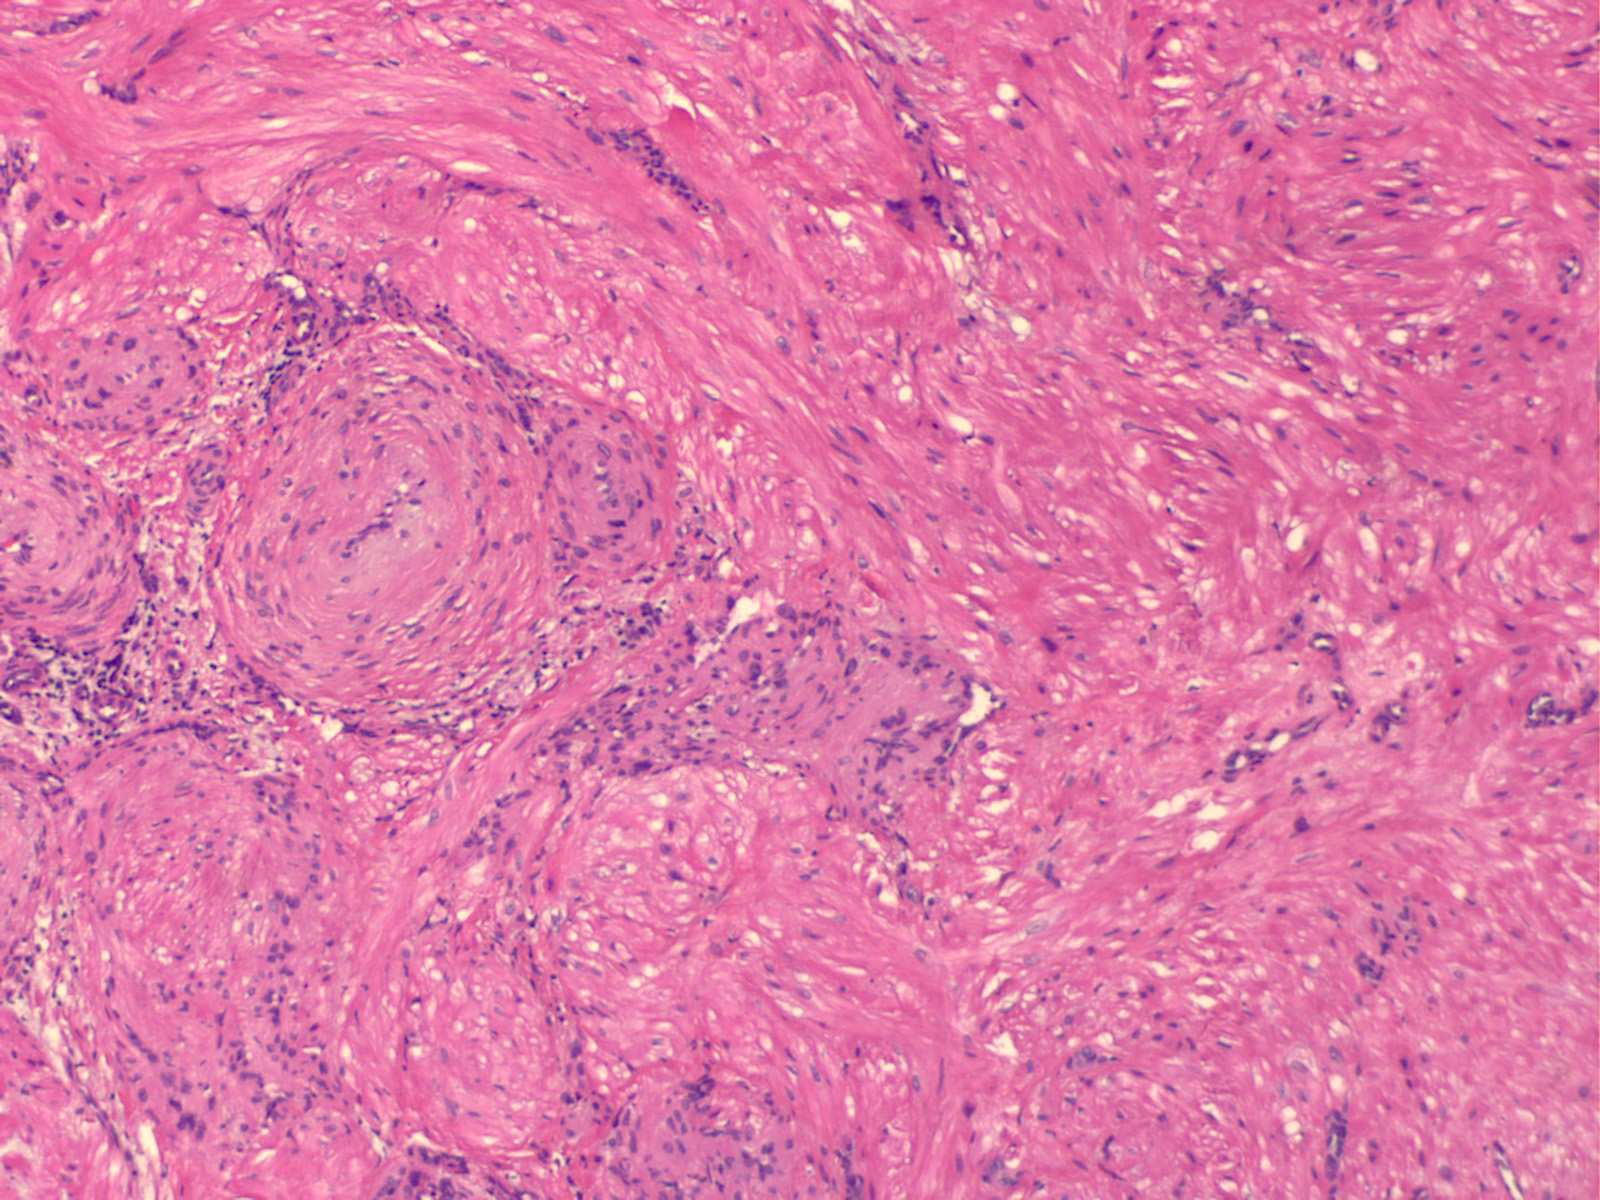

Angioleiomyoma =العضلوم الوعائي